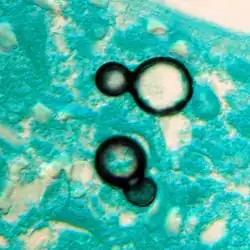

Once suspected, the diagnosis of blastomycosis can usually be confirmed by demonstration of the characteristic broad-based budding organisms in sputum or tissues by KOH prep, cytology, or histology.[27] Tissue biopsy of the skin or other organs may be required to diagnose extra-pulmonary disease. Blastomycosis is histologically associated with granulomatous nodules.

-

Granuloma with early suppuration. The fungal organisms are difficult to recognize at this low magnification. -

Large yeast-like fungi seen within giant cells at arrows. -

Large yeast-like fungi seen within giant cells at arrows. Budding yeasts in the cytoplasm of giant cells at the arrows. Broad-based budding and double-contoured cell walls are seen in the giant cell in the center are characteristic of Blastomyces dermatitidis. -